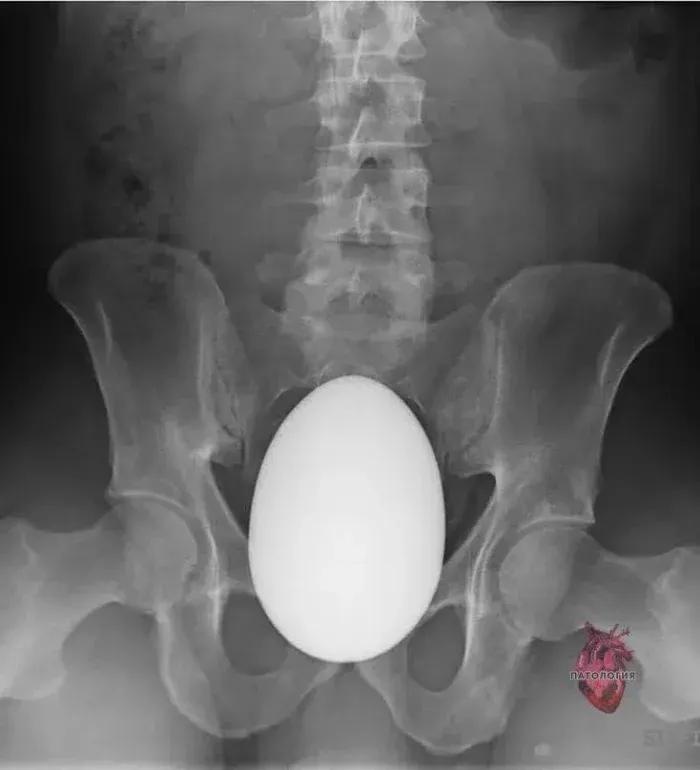

塞进去的东西就比较五花八门了,沐浴露、胡萝卜、鸵鸟蛋、水果刀、啤酒瓶,甚至还有活物……

塞进去的异物就比较难治疗了,一般是先需要医生进行肛门指检,再选择适宜的手术方式。通俗点说,就是手掏大便,看看异物深浅。